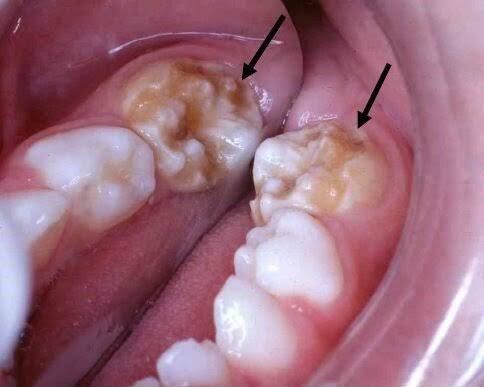

Enamel hypoplasia

Hypoplastic teeth, also known as enamel hypoplasia, is when your enamel has not formed properly or has formed incorrectly. There are many reasons why this might happen, including diseases, prenatal issues, and environmental conditions